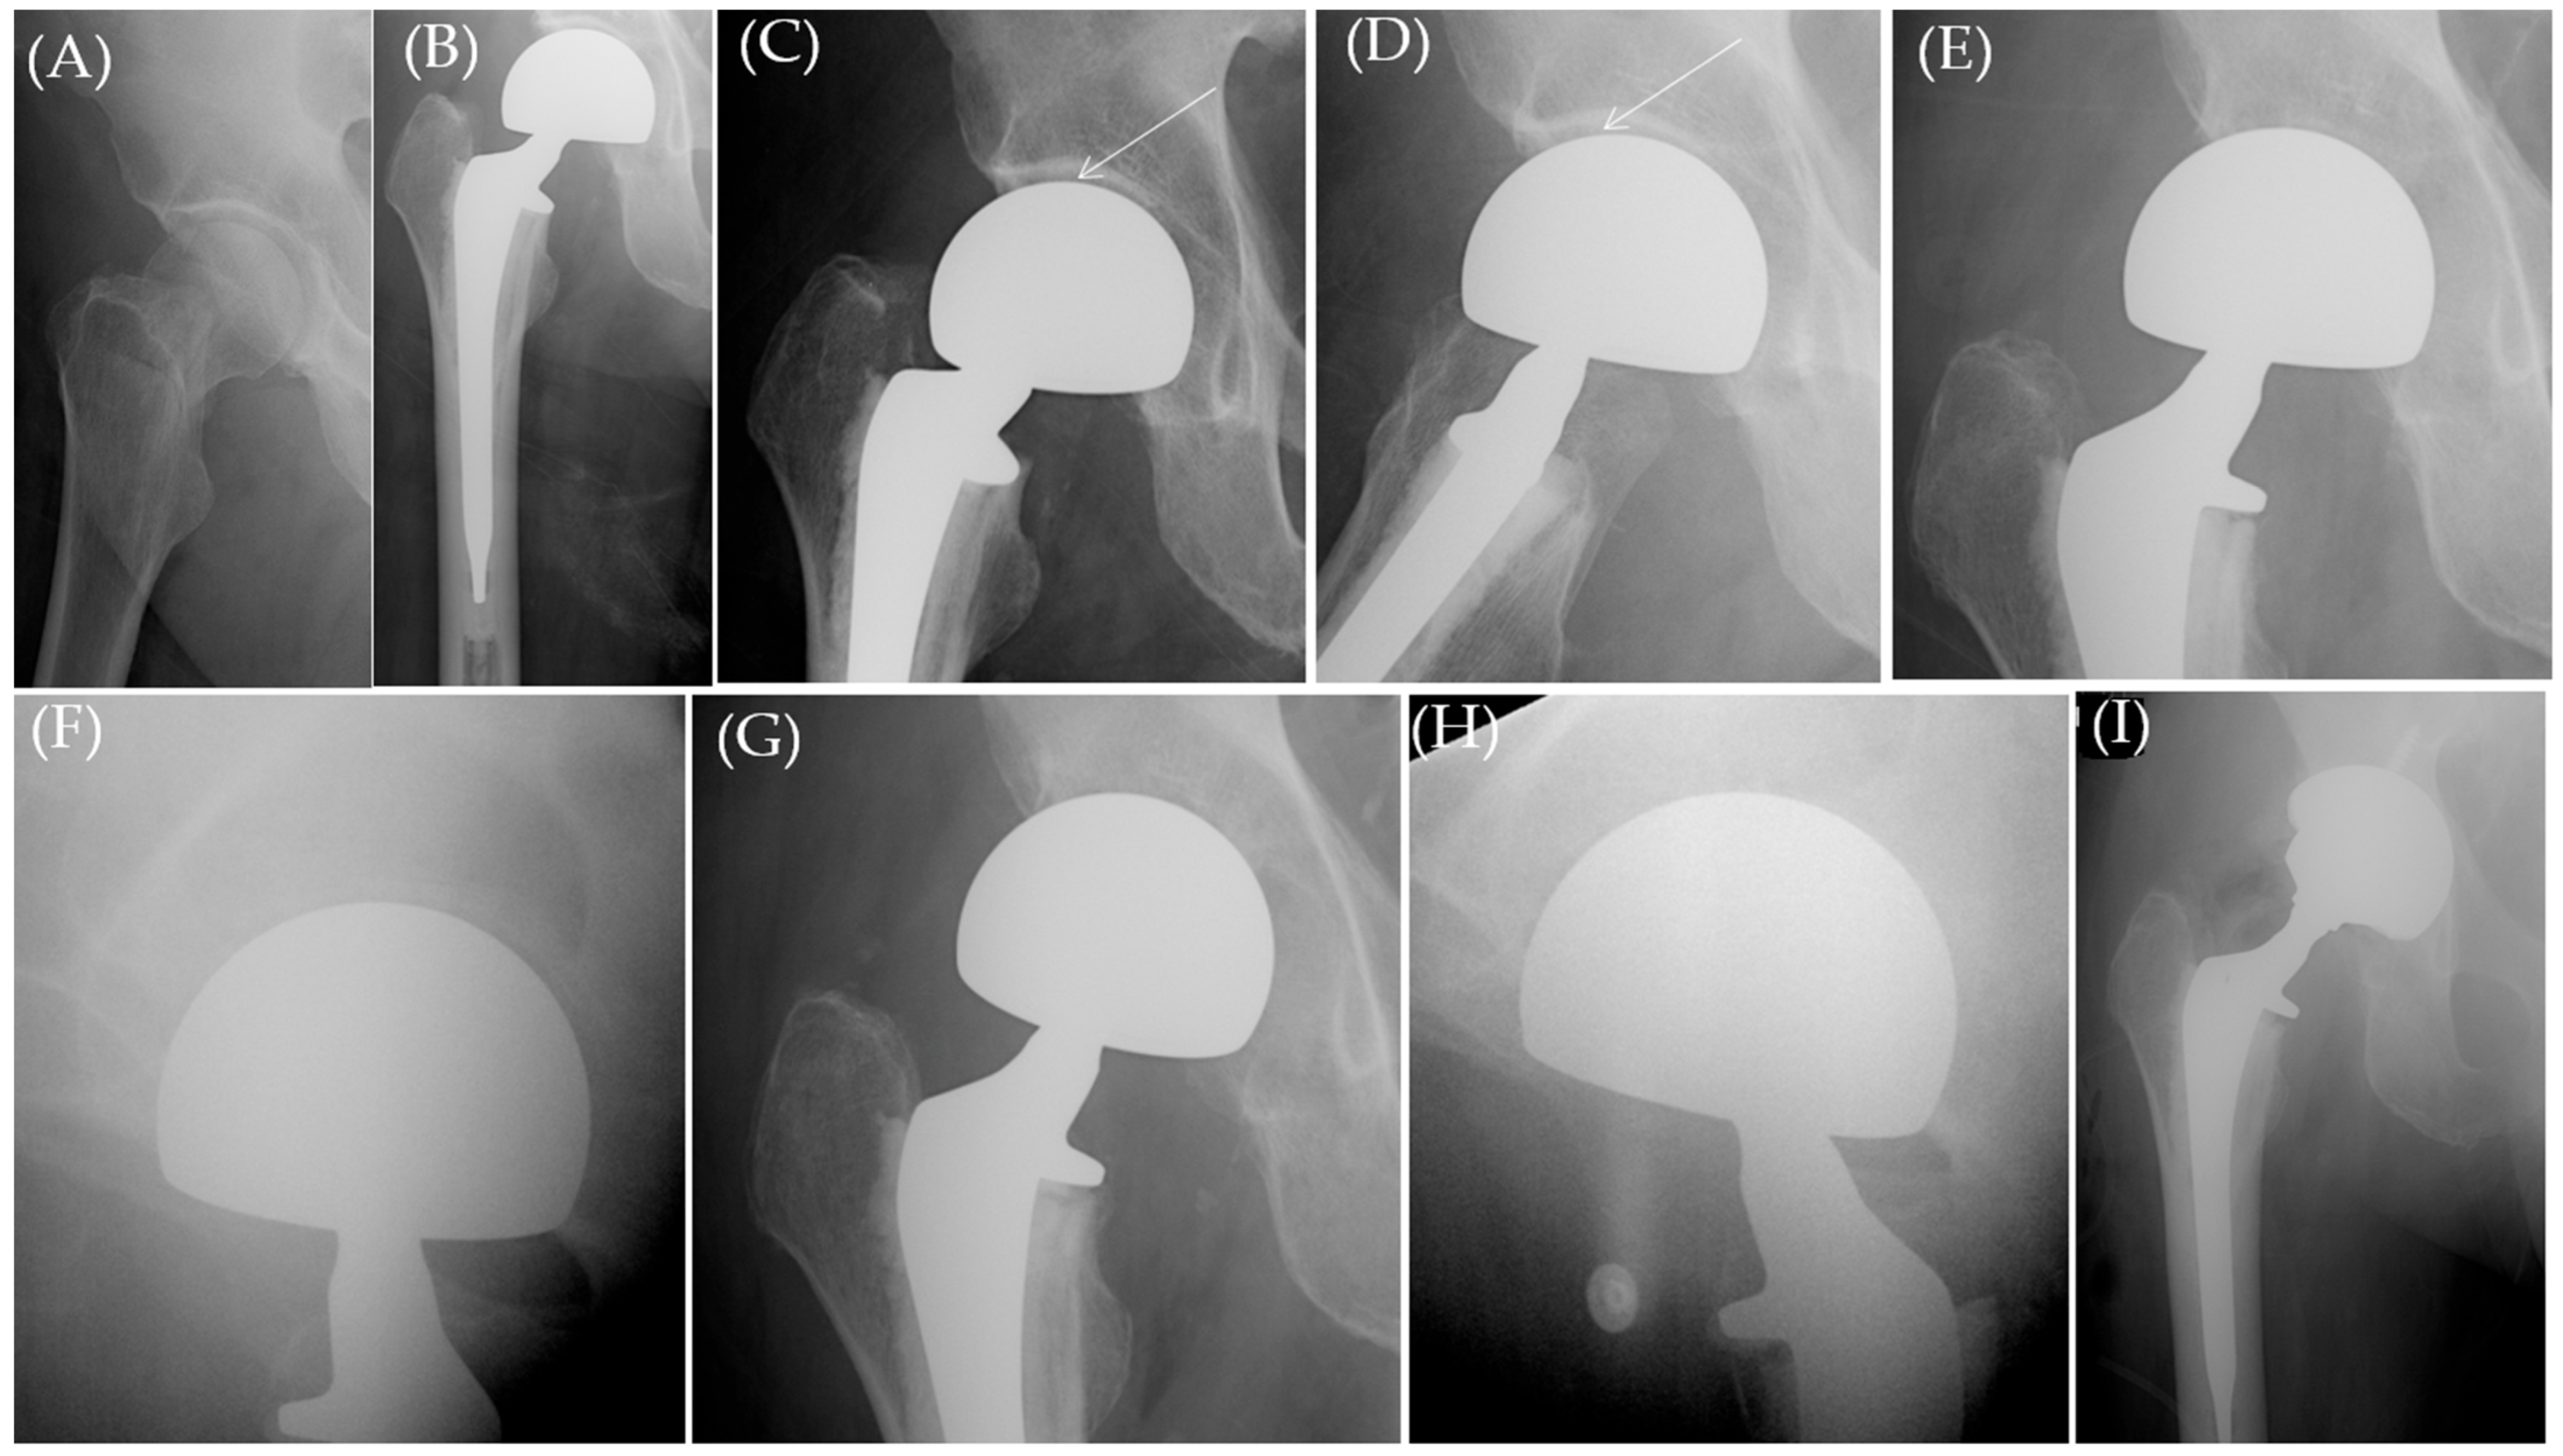

| Pt | Sex | Age (Y) | BMI | Implant Type | Symptomatic Acetabular Erosion per Implant Type & Statistical Comparison | Femoral Head Size | Stem Collared(C) /Uncollared (U) | Time Until Presentation (Pain) (M) | Medical Comorbidities | Management | Follow-Up (M) from the Index HA Surgery |

|---|---|---|---|---|---|---|---|---|---|---|---|

| 1 | F | 83.7 | 25 | UNI | 5/1109 (0.45%) | 46 | C | 11.54 | Conservative | 25.4 M | |

| 2 | F | 80.2 | 26 | UNI | 50 | C | 4.17 | Hypothyroid, Dementia, MS | THA | Died after 79.3 M | |

| 3 | F | 83.3 | 18.08 | UNI | 44 | C | 1.48 | Hypothyroid | Conservative | 69 | |

| 4 | F | 79.78 | 26 | UNI | 48 | U | 35.4 | Conservative | 47.5 | ||

| 5 | F | 66.89 | 26.54 | UNI | 48 | U | 2.76 | Conservative | 43.6 | ||

| 6 | F | 64.7 | 19.54 | BIP | 7/1368 (0.5%) Chi-square test: p = 0.8 (not statistically significant) | 48 | C | 4.3 | Osteoporosis | THA | 146.25 |

| 7 | F | 61.78 | 24.11 | BIP | 53 | C | 146.48 | Osteoporosis, Hypothyroid | Conservative | Died after 150 M | |

| 8 | F | 66.19 | 23.81 | BIP | 44 | C | 18.19 | Heavy Smoking, COPD | THA | Died after 31.9 M | |

| 9 | M | 47.1 | 22.46 | BIP | 40 | C | 61.6 | Spastic CP | Conservative | 177 M | |

| 10 | M | 76.58 | 27 | BIP | 54 | C | 2.5 | COPD, Epilepsy | THA | Died after 143.88 M | |

| 11 | M | 66.4 | 28 | BIP | 50 | C | 15.36 | THA | 215 M | ||

| 12 | M | 91.99 | 26.71 | BIP | 54 | C | 3.22 | Conservative | Died after 6 M |